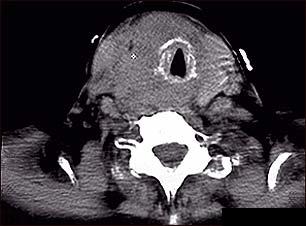

Cancerul tiroidian